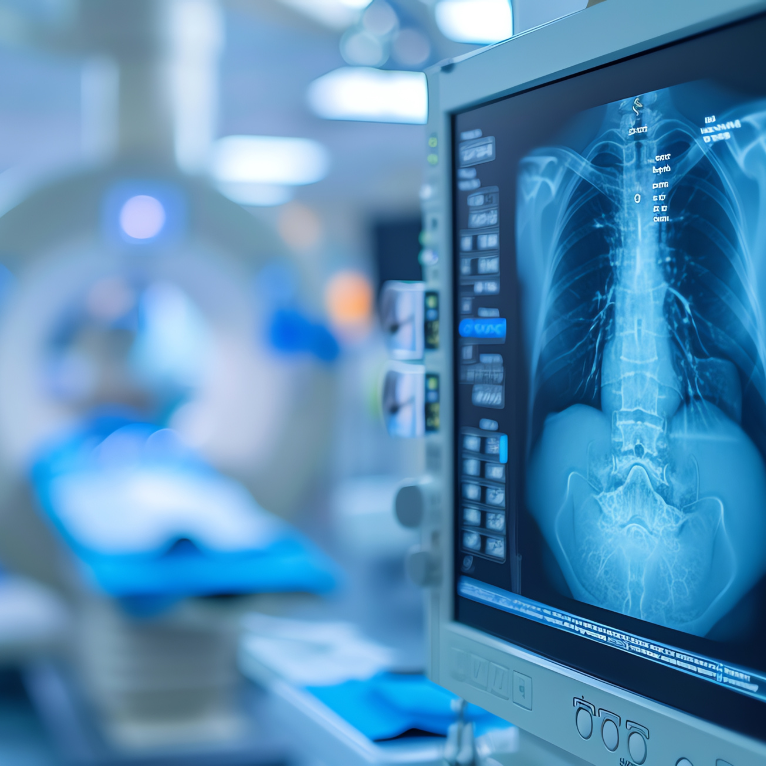

Medcy Hospitals provides advanced radiology and diagnostic imaging services for fast, accurate diagnosis, supporting effective treatment planning and improved patient outcomes.

Advanced diagnostic imaging allows doctors to visualise internal organs, tissues and structures in high detail-helping detect disease early, assess severity and guide the most effective treatment plans.

At Medcy Hospitals, our imaging services support a wide range of medical and surgical specialties through accurate, high-resolution scans.

High-resolution imaging technologies such as MRI, CT scans, ultrasound and digital X-rays are used to examine internal structures in detail.